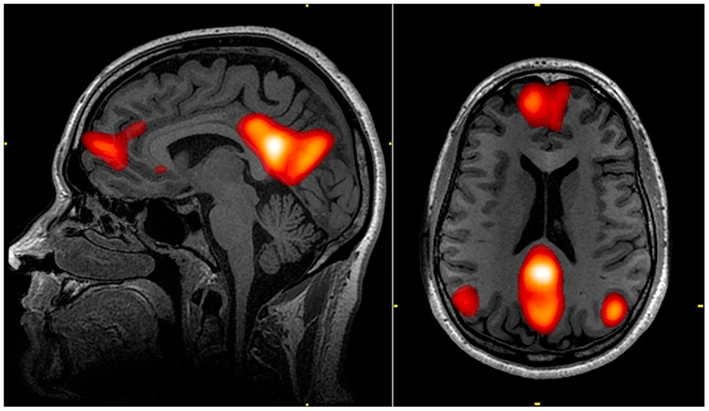

This isn’t metaphorical. It’s measurable. fMRI studies show that when experienced meditators enter meditative states, the regions of the DMN show significantly reduced activity compared to non-meditators. The neural regions that were busily generating self-referential narratives become less active.

In 2011, researchers at the University of Montreal led by Judson Brewer conducted a landmark study examining the relationship between meditation experience and DMN activity. They scanned experienced meditators while they meditated and during rest periods.

The finding was striking: during meditation, the DMN showed significantly reduced connectivity. The regions that normally communicate with each other to generate self-referential narratives were less synchronized. And remarkably, the amount of DMN deactivation correlated with meditation experience. The more hours someone had meditated, the more their DMN quieted during meditation.

But even more significantly: experienced meditators showed reduced DMN activity even during rest periods—when they weren’t actively meditating. Their baseline DMN activity had actually changed. Their brains had been trained to be less self-referential.